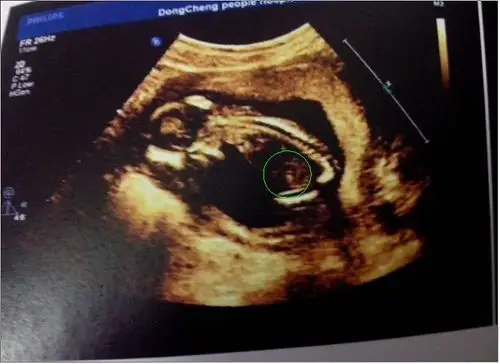

看不懂啊,这样能看男孩女孩吗?

思维的看不懂,彩超的男孩是明显的小鸡鸡,女孩的是3条小白线!

大家帮我看看彩超照片是男孩女孩?

有会看b超图的姐们吗?看看这里有木有小jj

二维彩超怎么看啊?我宝宝脸怎么看?这图是拍的准确位置是哪里?